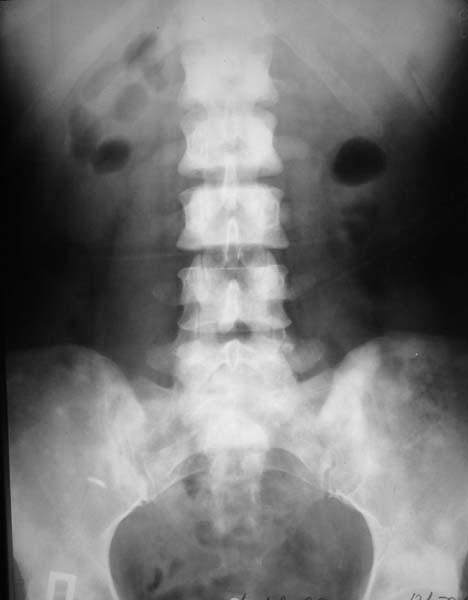

При МРТ (29.10.06) обнаружены диффузно-очаговые изменения в пояснично-крестцовом отделе позвоночника предположительно вторичного характера.

В октябре 2006 г. по поводу маточного кровотечения (менопауза 4 мес.) выполнено УЗИ - гиперплазия эндометрия, полипоз. Операция - удаление полипа, выскабливание полости матки. Цитологический анализ - пласты переходного климактерического эндометрия.Проведено комплексное исследование. В приложении: рентгенограммы и томограммы поясничного отдела позвоночника; радиологические исследованиямолочной железы, ЖКТ, почек, грудной клетки, анализы.УЗИ (18.12.06.) щитовидной железы, молочных желез - без патологии (умеренный фиброз по ходу млечных протоков).

Остеосцинтиграфия 4.12.06. - активный остеобластический процесс в поясничном, нижнегрудном отделах позвоночника, костях таза.Местными онкологами онко-процесс исключен. Фтизиатрический и онкогематологический диагнозы исключены.